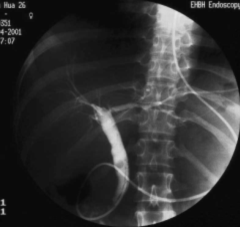

急性化脓性胆管炎怎样通过内镜(ERCP)“无切口”治疗?

急性化脓性胆管炎发病急、病情危重。典型症状为Charcot三联征,即腹痛、高热、黄疸。有较高的发病率和死亡率,尤其在老年病人中。治疗目的在于抢救病人生命,手术力求简单有效。内镜下鼻胆管引流术能紧急解除胆道梗阻并引流,及早而有效的降低胆道内压力。通过鼻胆管可以为胆管炎患者引流减压、预防胆结石嵌顿、冲洗胆道、便于观察病情变化、随时进行诊断。